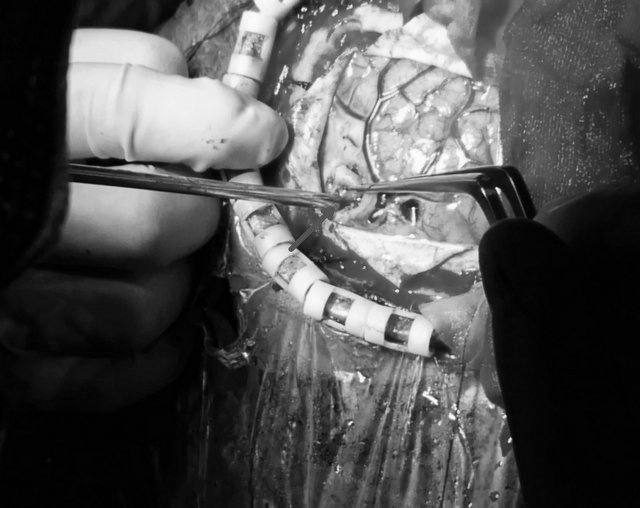

在医院的大力支持下,由神经外科一病区寿记新主任牵头组织了院内多学科会诊,决定采用超声实时引导下脑肿瘤切除的新技术。在神经外科专家以及麻醉、超声专家的共同努力下,寿记新主任亲自主刀,付旭东副主任协助,通过超声精确定位,准确的找到了肿瘤(图3),同时避开了重要的神经、血管,顺利全切病变组织(图4),术后李先生各项生命体征正常,手术获得圆满成功。术后一周,言语、偏瘫逐步恢复正常,影像复查显示肿瘤切除完整,无副损伤(图5)。

图3

图4